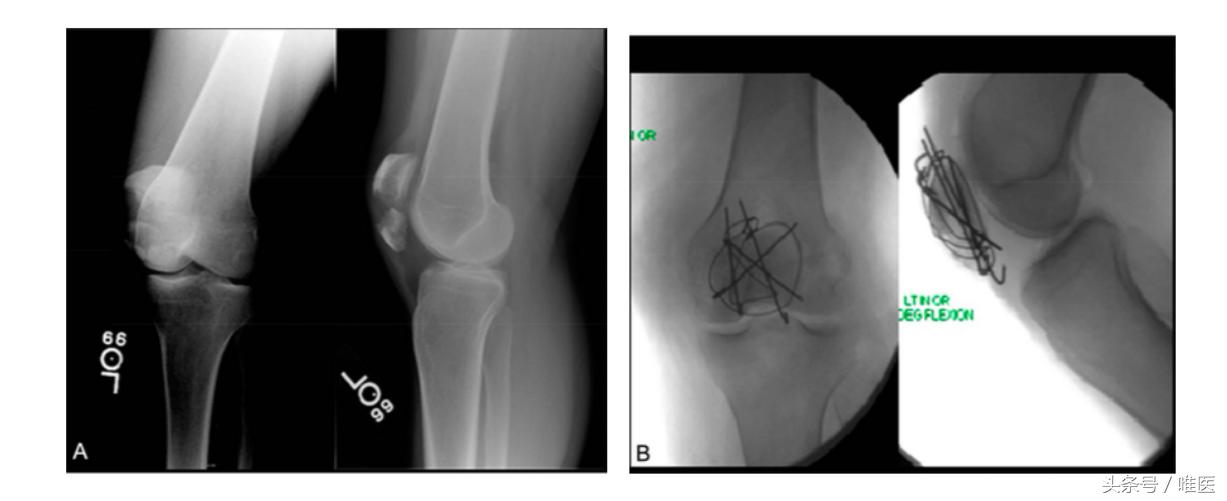

患者术前常规预防性抗生素使用,仰卧位消毒铺巾后,前正中切口暴露骨折,直视下判断骨折程度、主要骨折线位置及评估是否可使用多重钢丝复合张力带固定技术。前述复杂性髌骨骨折为本手术方法的适应征。术中利用2枚或2枚以上1.6mm克氏针固定主要横行骨折线,再利用额外1.6mm克氏针固定其他主要骨折平面,18号胸骨钢丝“8”字形多重张力带结合钢丝环扎技术固定主要骨折块(图1),必要的情况下可3.5mm实心或4.0mm空心螺钉辅助固定骨折块。骨折固定稳妥充分冲洗伤口,逐层关闭切口。

图1多重钢丝复合张力带技术开放复位内固定粉碎性髌骨骨折:(A)术前髌骨骨折正侧位片;(B)术中透视示克氏针固定主要骨折线平面+张力带及钢丝环扎加固内固定结构。